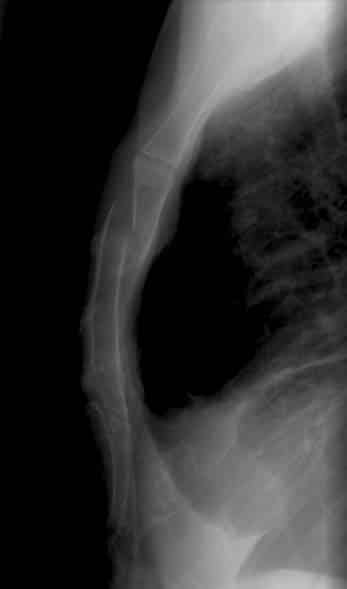

The sternum (or breastbone) is a flat bone located at the anterior aspect of the thorax. It lies in the midline of the chest and has a ‘T’ shape. As part of the bony thoracic wall, the sternum helps protect the internal thoracic viscera – such as the heart, lungs and oesophagus. In this article, we shall look at the osteology of the sternum – its constituent parts, articulations, and clinical correlations. By Anatomography [CC-BY-SA-2.1-jp], via Wikimedia Commons Fig 1Anatomical position of the sternum in the body thorax. Pro Feature - 3D Model You've Discovered a Pro Feature Access our 3D Model Library Explore, cut, dissect, annotate and manipulate our 3D models to visualise anatomy in a dynamic, interactive way. Learn More Parts of the Sternum The sternum can be divided into three parts; the manubrium, body and xiphoid process. In children, these elements are joined by cartilage. The cartilage ossifies to bone during adulthood. Manubrium The manubrium is the most superior portion of the sternum. It is trapezoid in shape. The superior aspect of the manubrium is concave, producing a depression known as the jugular notch – this is visible underneath the skin. Either side of the jugular notch, there is a large fossa lined with cartilage. These fossae articulate with the medial ends of the clavicles, forming the sternoclavicular joints. On the lateral edges of the manubrium, there is a facet (cartilage lined depression in the bone), for articulation with the costal cartilage of the 1st rib, and a demifacet (half-facet) for articulation with part of the costal cartilage of the 2nd rib. Inferiorly, the manubrium articulates with the body of the sternum, forming the sternal angle. This can be felt as a transverse ridge of bone on the anterior aspect of the sternum. The sternal angle is commonly used as an aid to count ribs, as it marks the level of the 2nd costal cartilage. Body The body is flat and elongated – the largest part of the sternum. It articulates with the manubrium superiorly (manubriosternal joint) and the xiphoid process inferiorly (xiphisternal joint). The lateral edges of the body are marked by numerous articular facets (cartilage lined depressions in the bone). These articular facets articulate with the costal cartilages of ribs 3-6. There are smaller facets for articulation with parts of the second and seventh ribs – known as demifacets. Xiphoid Process The xiphoid process is the most inferior and smallest part of the sternum. It is variable in shape and size, with its tip located at the level of the T10 vertebrae. The xiphoid process is largely cartilaginous in structure, and completely ossifies late in life – around the age of 40. In some individuals, the xiphoid process articulates with part of the costal cartilage of the seventh rib. By TeachMeSeries Ltd (2025) Fig 2The articulations and parts of the sternum. Clinical Relevance Fractures of the Sternum Sternal fractures are associated with severe blunt trauma to the chest, such as in a vehicular accident. They are relatively uncommon. Typically, the sternum will break into several pieces – this type of fracture is classified as a comminuted fracture. The most common site of fracture is the manubriosternal joint – where the manubrium meets the body of the sternum. Despite the degree of damage to the sternum, the fragments are not usually displaced due to the attachment of the pectoralis muscles. Sternal fractures have a high mortality rate (25-45%). This is not due to the fracture itself, but usually as a result of heart and lung injuries, which are likely to occur simultaneously with the primary trauma. Because of this, it is crucial to check patients with sternal fractures for visceral injury. X-ray, CT and ultrasound are common investigations. By Life in the Fast Lane [CC BY-SA 4.0] Fig 3Lateral view of a displaced sternal fracture. Do you think you’re ready? Take the quiz below Pro Feature - Quiz The Sternum Question 1 of 3 Submitting... Skip Next Rate question: You scored 0% Skipped: 0/3 1800 More Questions Available Upgrade to TeachMeAnatomy Pro Challenge yourself with over 1800 multiple-choice questions to reinforce learning Learn More Rate This Article